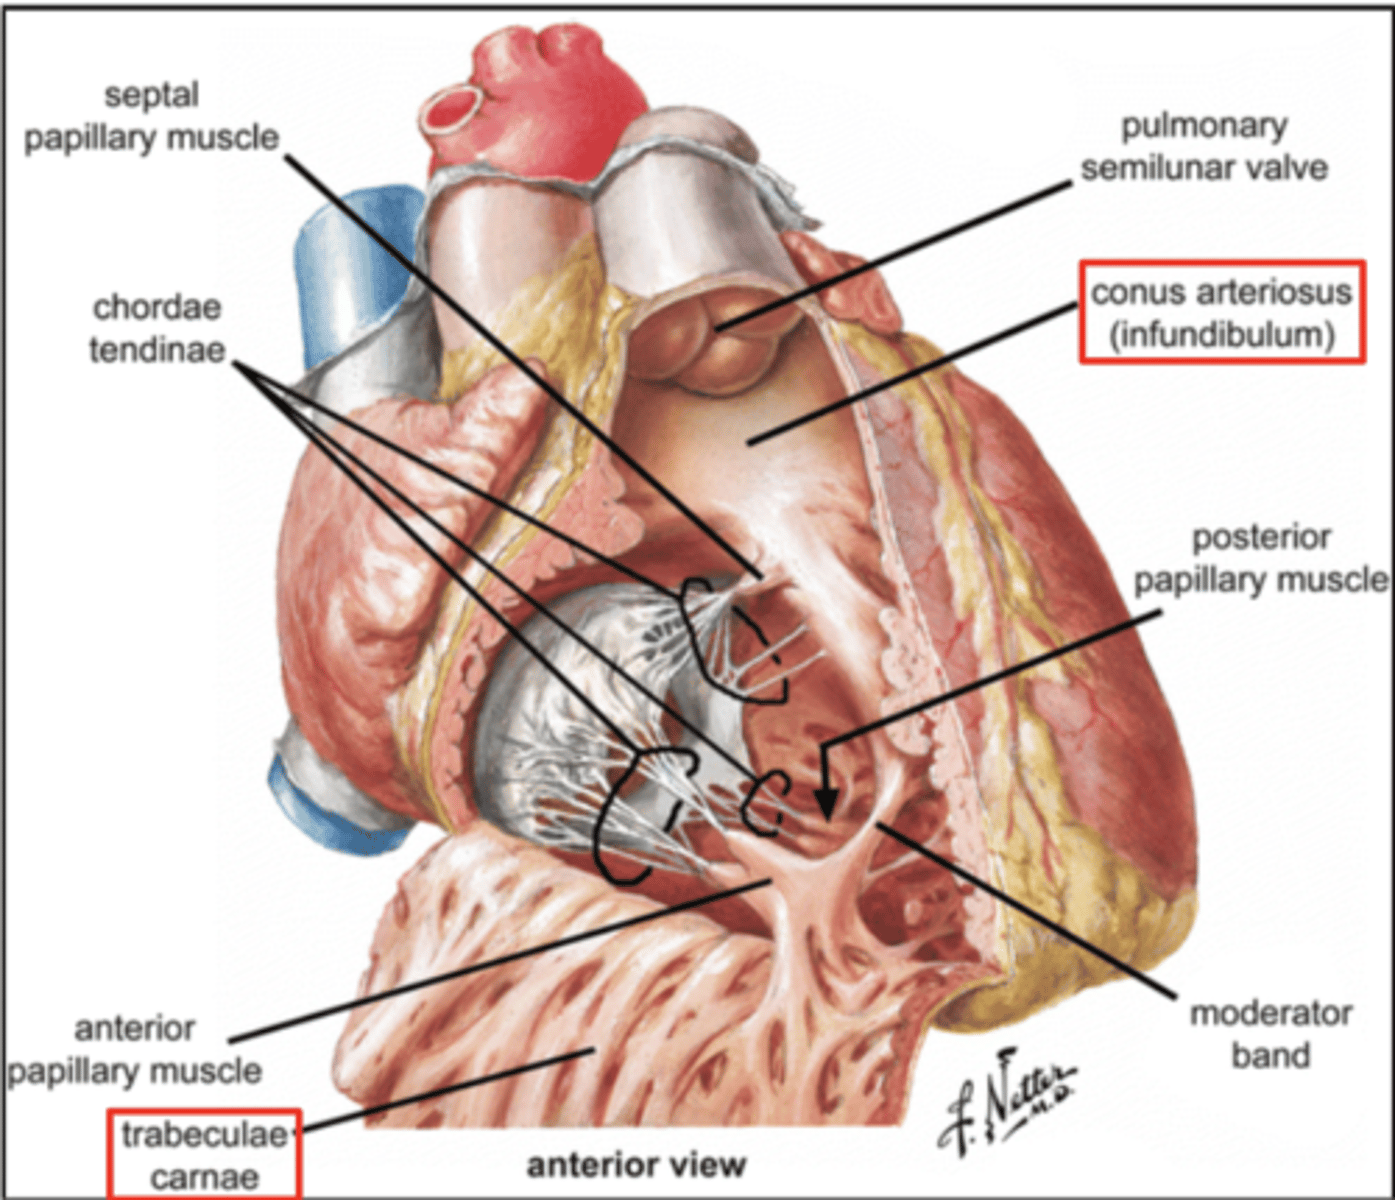

Describe the two portions of the medial/septal face/wall of the right ventricle.

infundibulum or outflow region or conus arteriosus (smooth and membranous)

trabeculae carnae (muscular and irregular)

What are the 3 cusps of the tricuspid valve?

Anterior

Posterior

Septal

What connect the cusps of the valve a to papillary muscles in the

right ventricle?

Chordae tendinae

With the contraction of the walls of the ventricle what's the action of the papillary muscles?

contract as well

With the contraction of papillary muscles what will be happen with the valve?

Close

What is the septomarginal trabeculae (or moderator band)?